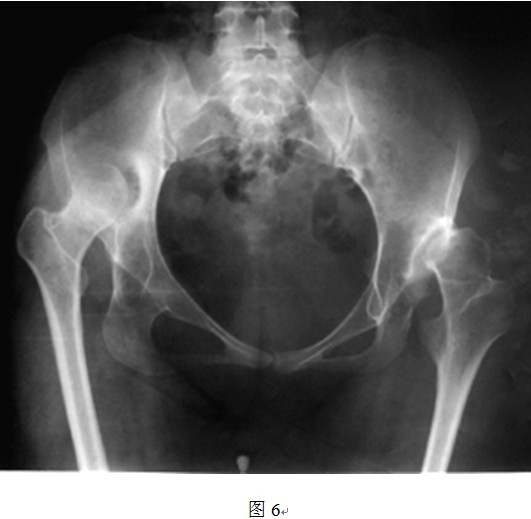

5. THRA不能有效延长肢体

THRA另外一个先天不足就是,从假体本身的设计来看,THRA假体本身不存在延长肢体长度的功能。普通THR的股骨侧假体可通过使用加长头、组配式股骨颈等设计来延长肢体长度,而THRA置换股骨头后,股骨头颈的长度没有明显变化。因此,只能从改变髋臼位置来使得股骨头中心下移,达到部分恢复肢体长度的目的。但是,对于DDH来讲,存在多个不利于肢体长度恢复的因素。首先,DDH假臼形成或者原始髋臼非常浅,加之表面置换不切除头颈情况下阻碍术者视野,想要定位真正的髋臼旋转中心有时比较困难,髋臼下移不一定能够完全实现;其次,即使找到并定位了真臼的旋转中心,但因软组织挛缩严重,术中股骨侧无法充分下移,可能出现无法复位的问题(图6);另外,还有一些患者患侧股骨颈本身就发育短缩或者存在髋内翻(颈干角变小),即使恢复了真臼的旋转中心,股骨侧也可以顺利复位,但是患侧肢体仍旧较对侧短缩(如图13所示左侧股骨颈短缩且内翻,采用THRA无法恢复肢体长度)。

原位表面置换对右侧VI度发育不良延长肢体毫无用处,因股骨头及粗隆部上移过多,右侧肢体短缩缩严重,可能需要转子下截骨才能复位关节,不适合行THRA手术。